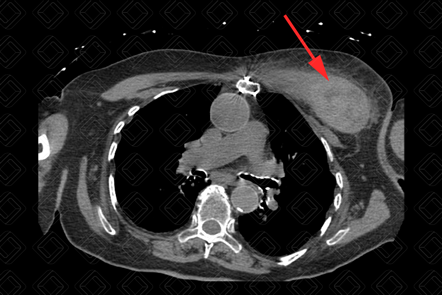

Texto alternativo para a imagem Figura 2. Créditos: Dra. Elazir Mota - Rio de Janeiro/RJ

Descrição das figuras 1, 2 e 3: Tomografia computadorizada de tórax evidenciando lesão heterogênea (seta vermelha) na musculatura peitoral esquerda, espontaneamente densa (densidade ao redor de 65 UH), compatível com hematoma. Paciente fazia uso crônico de anticoagulante.

• Tomografia computadorizada (TC): Observamos aumento volumétrico da musculatura acometida e conteúdo espontaneamente denso no estudo sem contraste (50-80 UH) (figura 1);